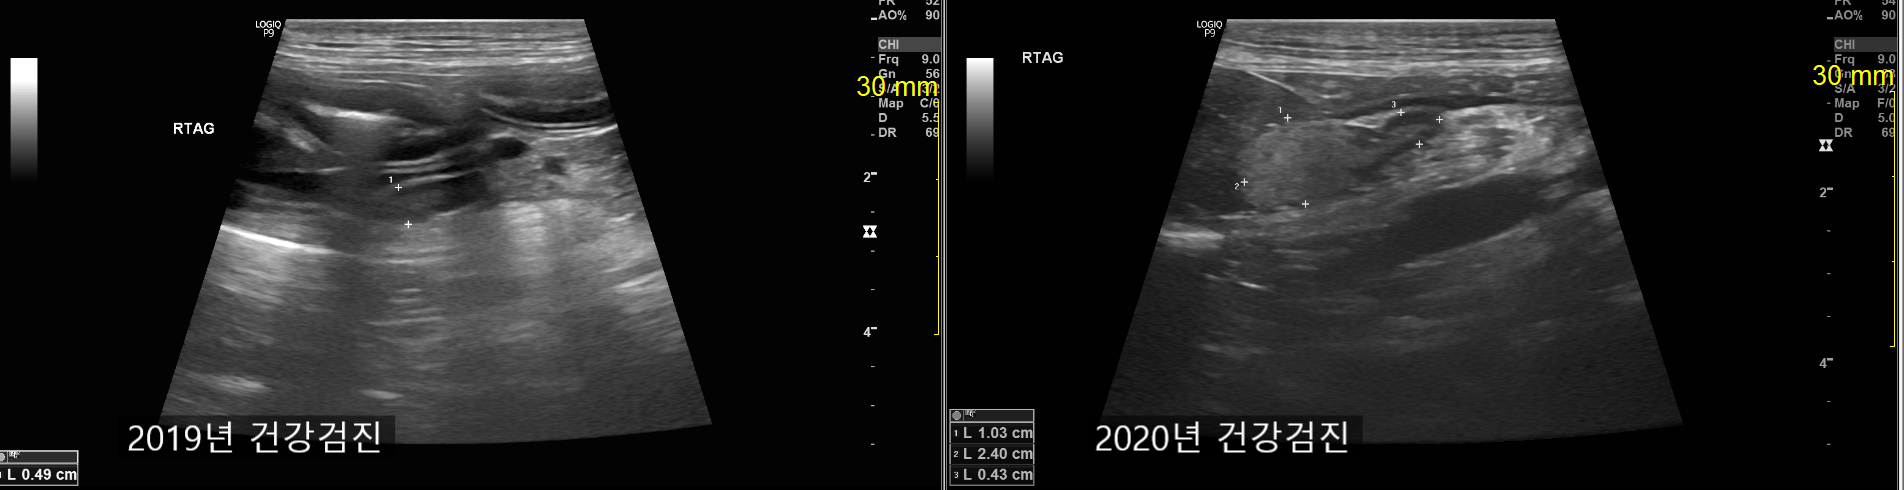

복부 초음파 검사상 대부분 큰 이상이 없었지만 부신의 종대가 확인이 되었습니다.

왼쪽 부신과 달리, 오른쪽 부신의 앞쪽 부분이 불규칙한 경계가 보이며 커져 있는 상태였습니다.

2019년 건강검진 당시 정상적이였던 오른쪽 부신과 비교해봤을때 크기가 확연히 커져있는 것을 볼 수 있었습니다.